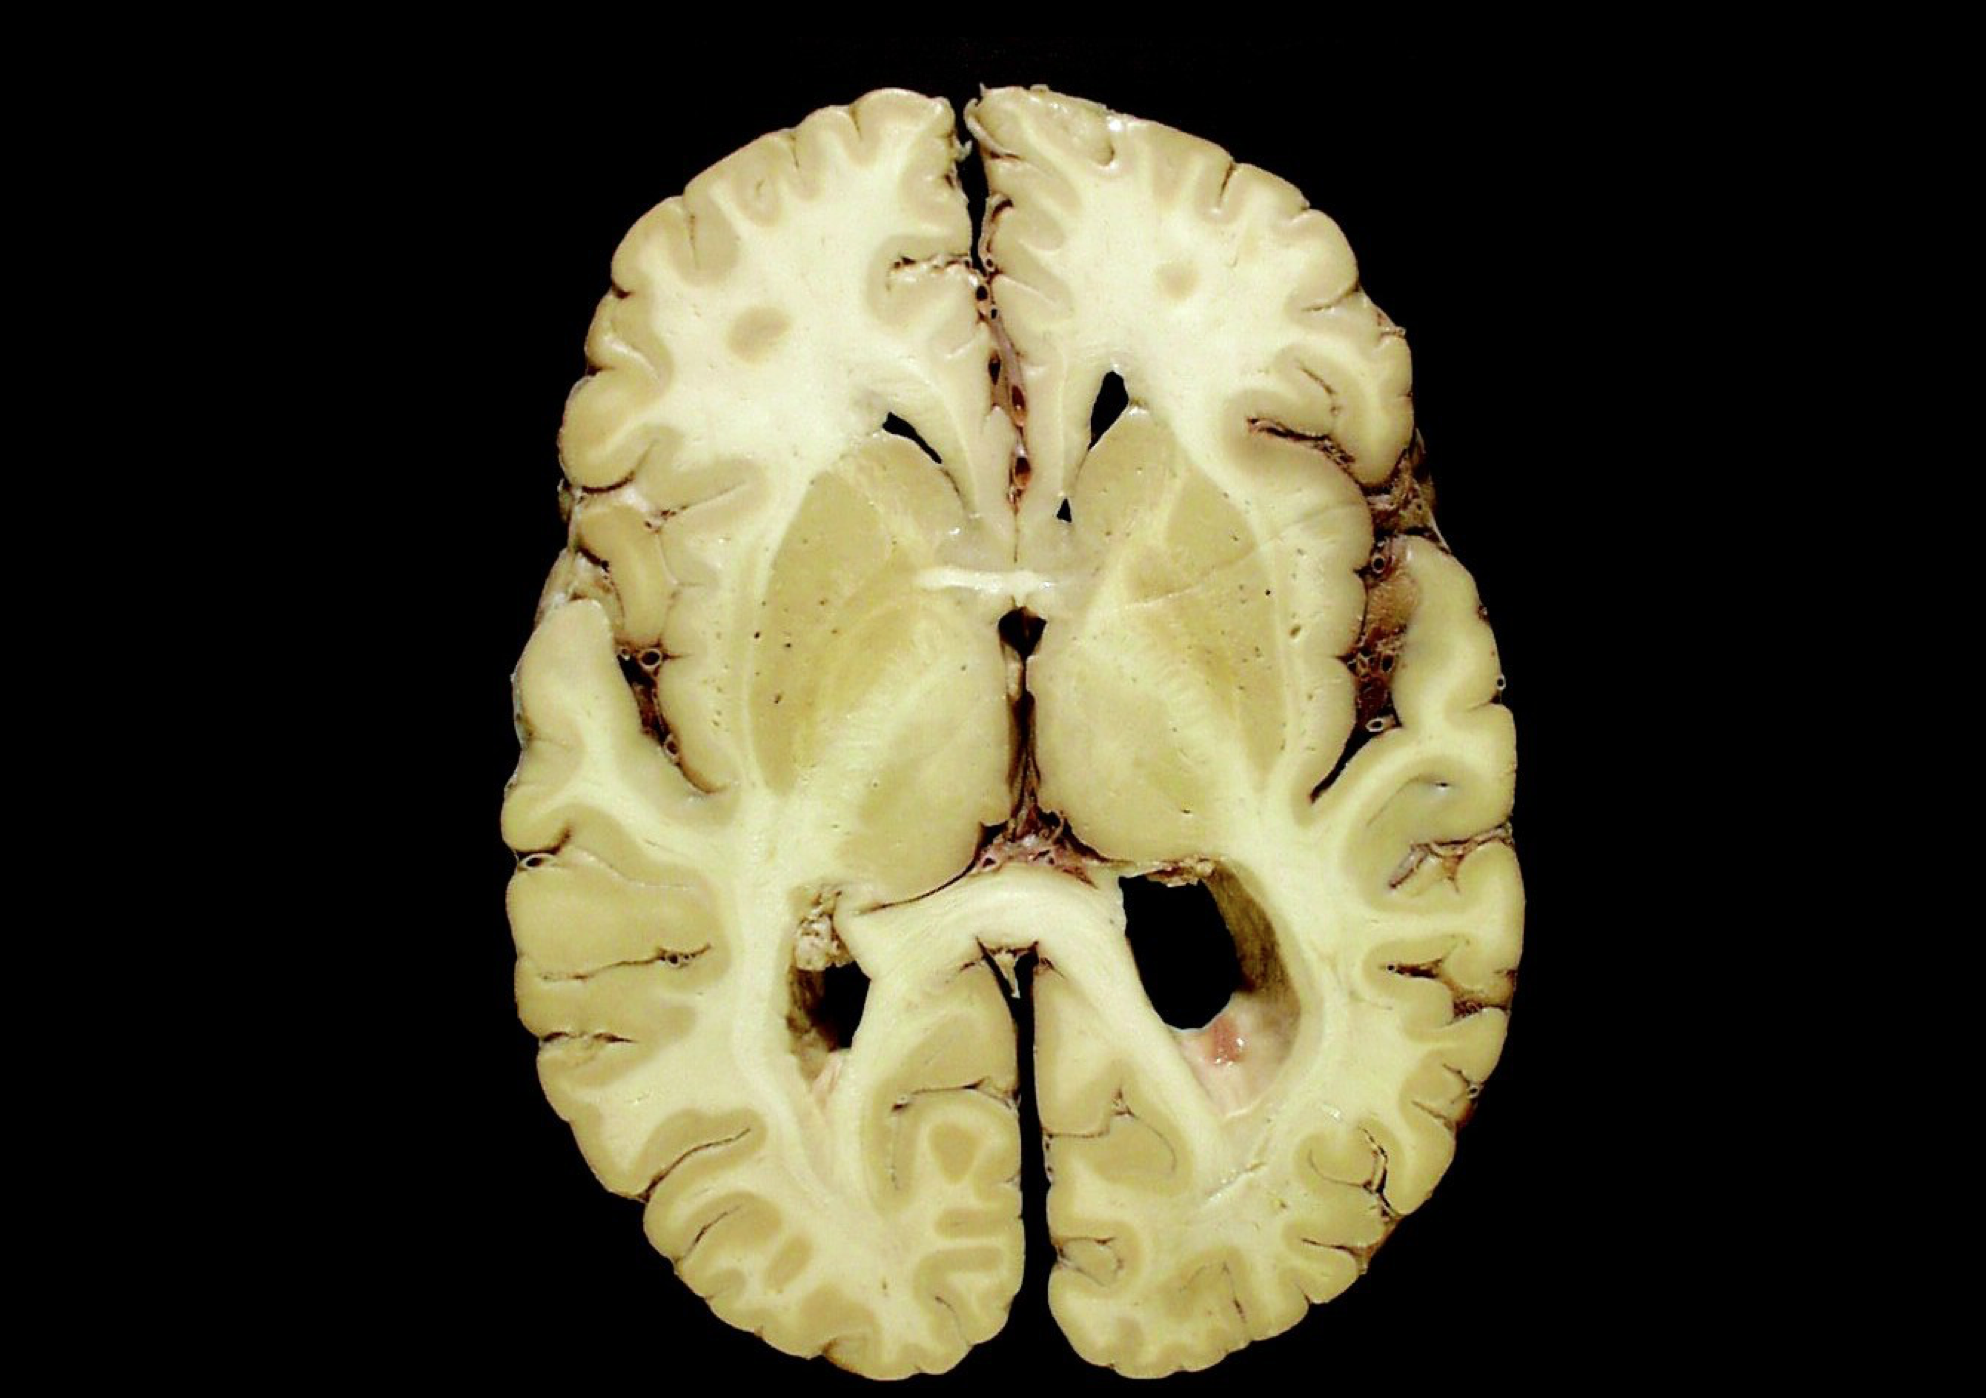

Gross Neuroanatomy, Part 1

Gross Neuroanatomy, Part 2